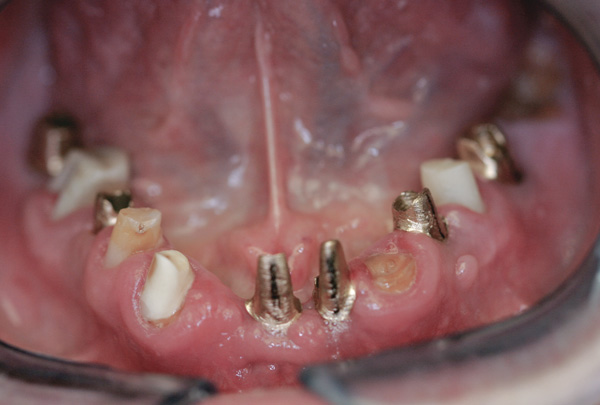

Background: This patient had a failing maxillary dentition and refused to wear a removable prosthesis. A staged approach was employed to retain some of his natural tooth abutments, and recession was noticed at the time of the impression for the second group of implants. Figure 1 shows the patient following insertion of the first set of implant custom abutments; the adjacent natural teeth are still present to support the provisional bridge. Seven months later, as shown in Figure 2, those first-stage custom abutments exhibited evidence of 1 mm to 3 mm of recession.

Results: A decision was made to re-prepare all of the abutments intraorally (Figure 3) so that all abutment margins would be at or below the gingival margin. (Of note, teeth Nos. 8 and 9, also shown in Figure 3, were later submerged for the case to be fully implant-supported.) While re-preparation greatly improved the esthetics of the final result, it required retraction cord placement, new impressions, and new castings.

Figure 2 After 7 months, the first-stage custom abutments exhibited evidence of 1 mm to 3 mm of recession.

Figure 2

Figure 3 Abutments re-prepared intraorally.

Figure 3